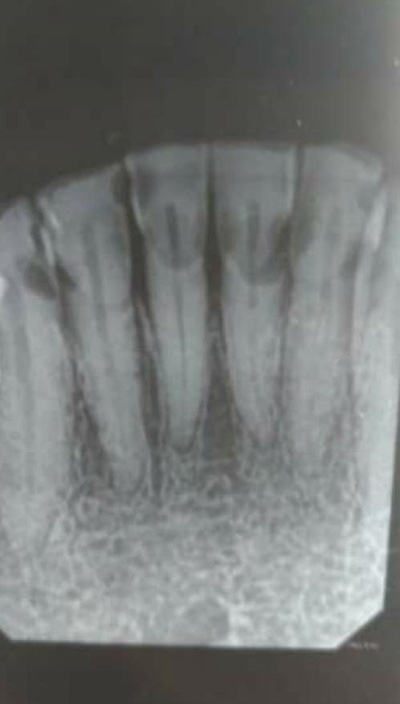

tipos de atendimentos - endodontia

Tratamento rápido e sem dor, combinando técnicas avançadas e tecnologia de ponta para garantir a preservação dos dentes e o sucesso a longo prazo.